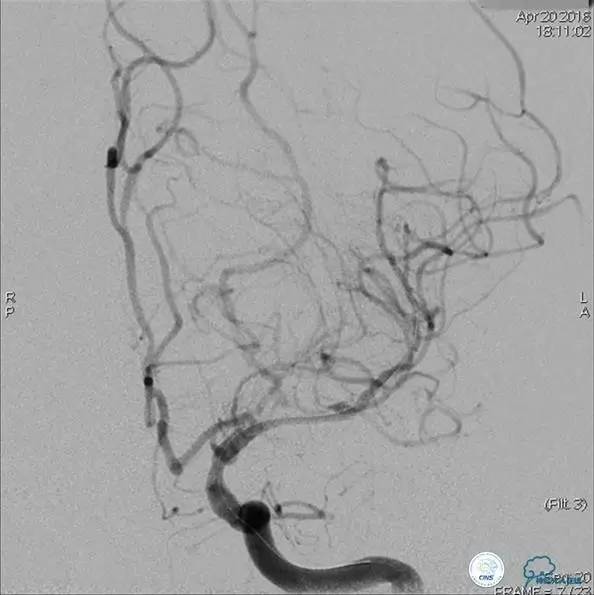

病例5

患者:49岁男性,左侧偏瘫1个月,药物治疗、康复训练效果不好,转我院,肌力0~1级。

core-clilnical明显不匹配,是介入开通的合适患者。

造影评价血管、判断闭塞段,微导丝小心穿过闭塞段,微导管造影,交换技术,球囊扩张,Enterprise支架。在后扩张时导丝刺破M3段血管,蛛网膜下腔出血(SAH)。

微导管进入破裂血管,栓塞弹簧圈1枚,出血停止,结束手术。继续双抗,术后2天肌力2级,神经功能恢复明显加快。

术后即刻和6天后CT,患者无明显临床症状。

半年后复查造影,无支架内再狭窄,可见弹簧圈,患者恢复至自己柱杖行走。